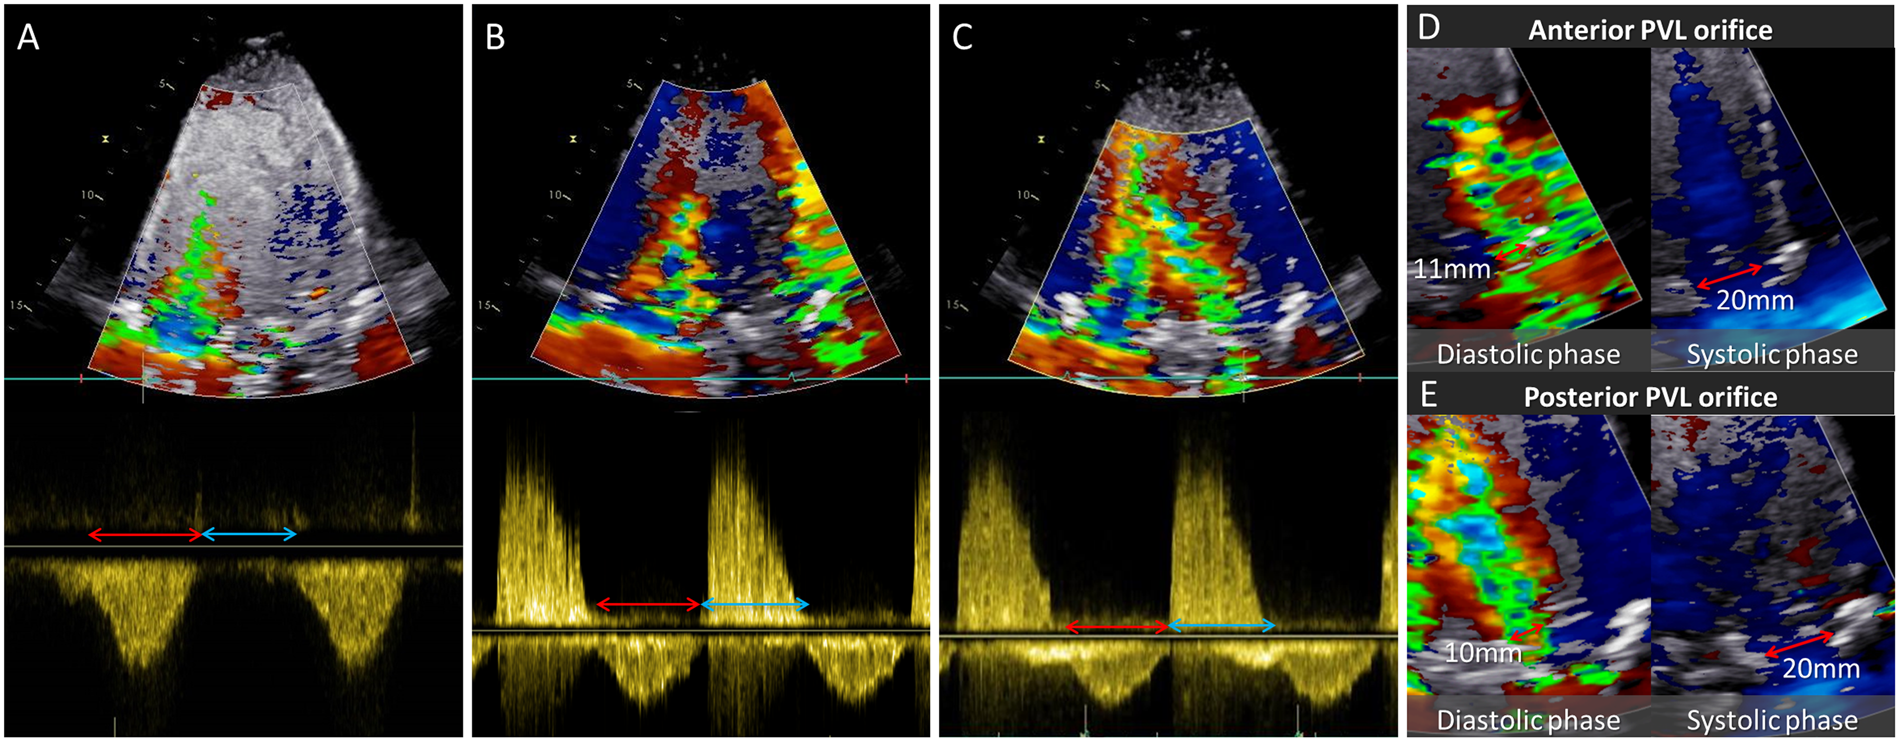

Figure 1

From: Intraventricular Vortex Interaction between Transmitral Flow and Paravalvular Leak

Color Doppler imaging, continuous Doppler echocardiography. (A–C) Color Doppler imaging and continuous wave (CW) Doppler echocardiography. Obvious regurgitant signal was observed in (B) and (C) and the interaction between the PVL jet and the transmitral flow was observed in (C). Red and blue arrows indicate systole and diastole, respectively. (D) and (E) Width of the PVL jet and outflow tract in anterior and posterior PVL case.